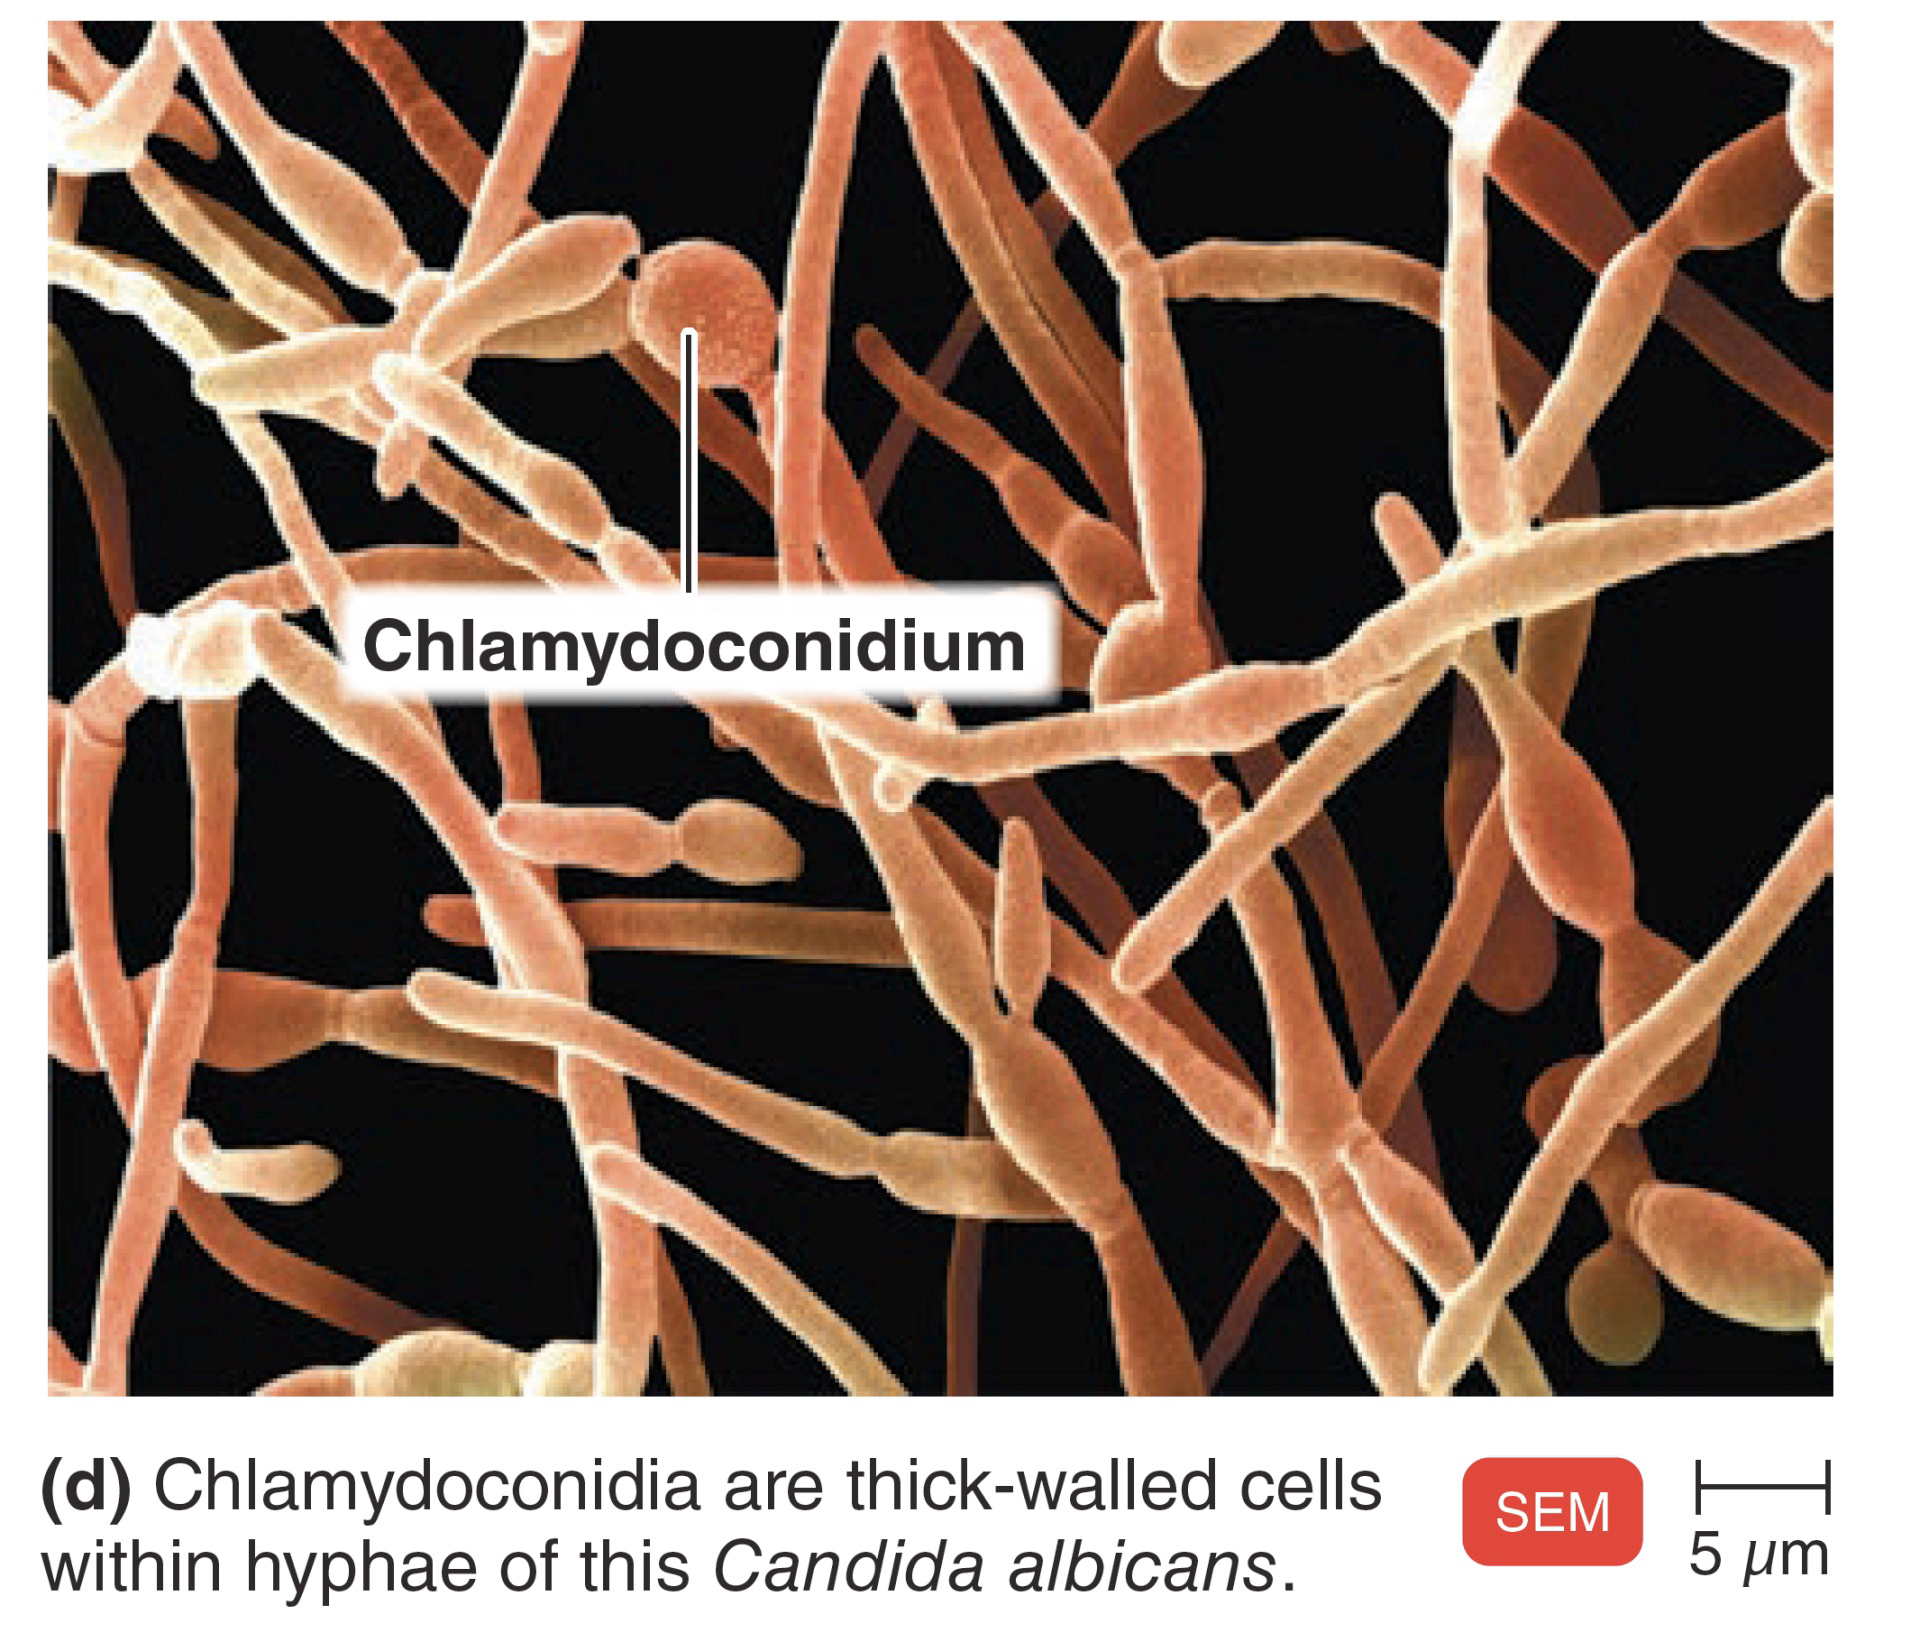

- Chlamydospore (厚膜孢子)

Candida albicans 白色念珠菌

- 70% 院內黴菌感染